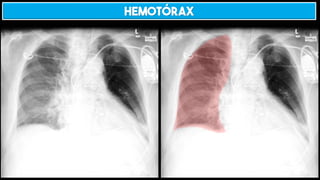

HEMOTÓRAX